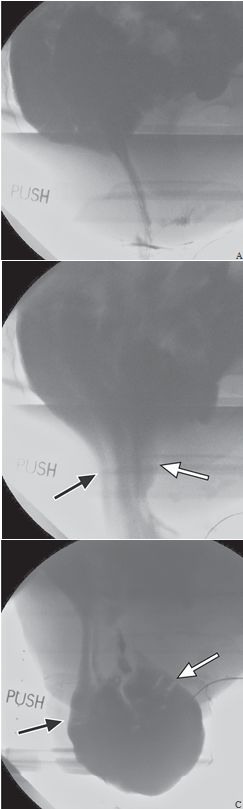

正常情况下肛直角在90°~110°。当排便开始时,肛直角会变钝,肛管变直。但有些患者会出现耻骨直肠肌悬带反常收缩,盆底松弛失败,引起排便梗阻,这种现象称为盆底失弛缓或者盆底痉挛(图1)。生物反馈技术治疗对一些患者有效。

图1 耻骨直肠肌悬带松弛功能受损,致盆底痉挛,阻碍排便。静息状态(A)、提肛状态(B)和力排状态(C)的排便造影图显示肛直角(箭)的变化,在提肛时应角度变小,力排时应角度变大。力排时耻骨直肠肌的压迹明显(C,箭),提示反常收缩